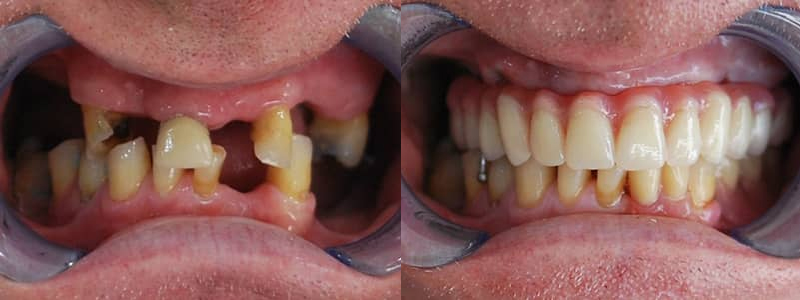

Treatment: Same Day Teeth & Cosmetic Dentures